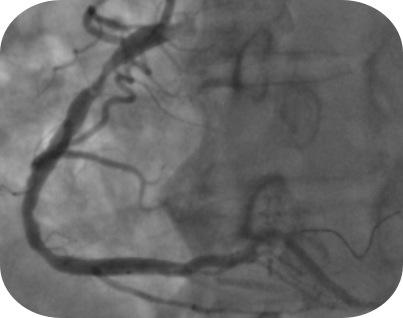

患者因急性冠脉综合征入院。冠脉造影提示其冠脉病变复杂,第一对角支近端闭塞,右冠状动脉(RCA)近段存在95%的重度狭窄伴血栓。面对如此复杂且危重的病情,团队决定启用先进的OCT技术来指导手术。

术前造影及OCT图像可见右冠脉局部大量白色血栓,伴局部破溃。